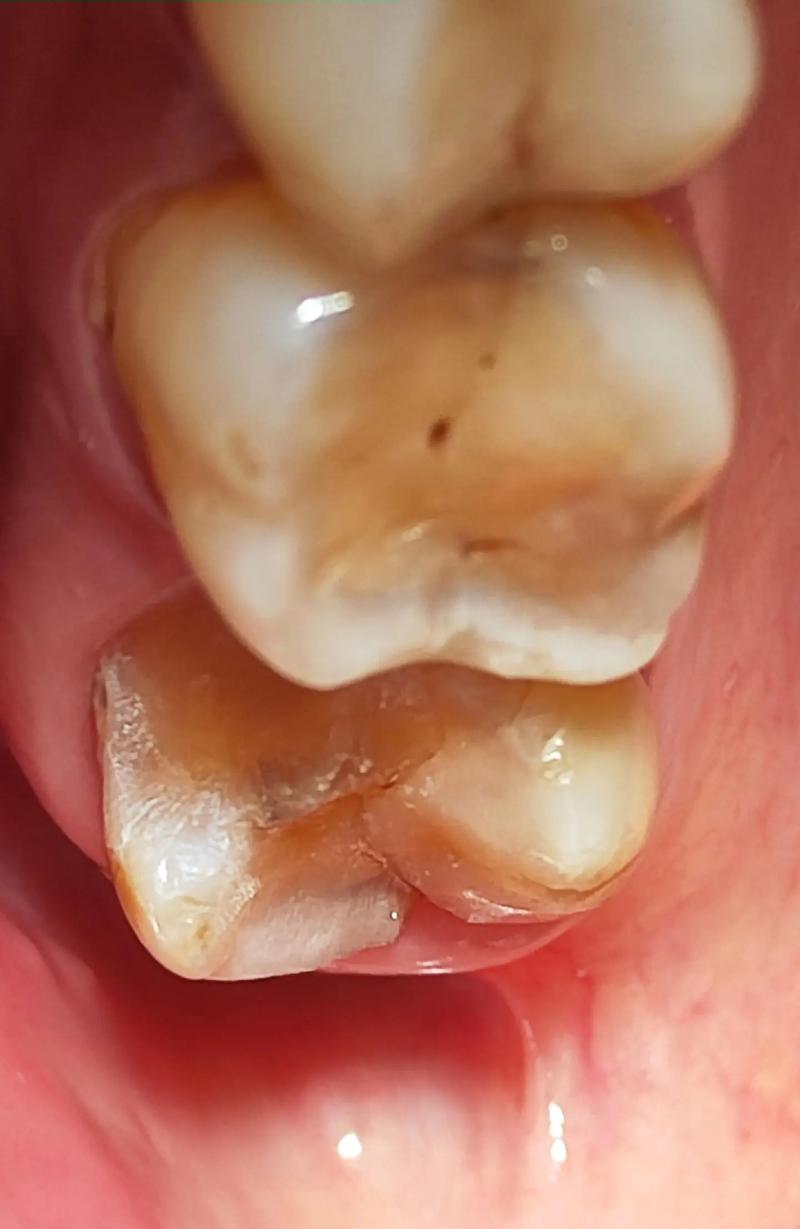

种植体植入位置/深度问题:

- 种植体植入过深: 如果种植体在手术时植入的位置过深(埋入骨组织过多),那么即使使用了标准高度的基台和牙冠,露出牙龈的部分(即牙冠临床冠高度)也会显得不够高。

- 骨量不足导致种植体位置不佳: 如果种植区域骨量不足,医生为了获得初期稳定性,可能会将种植体植入更深的位置,或者选择角度基台来补偿,但这有时也会影响最终牙冠高度。